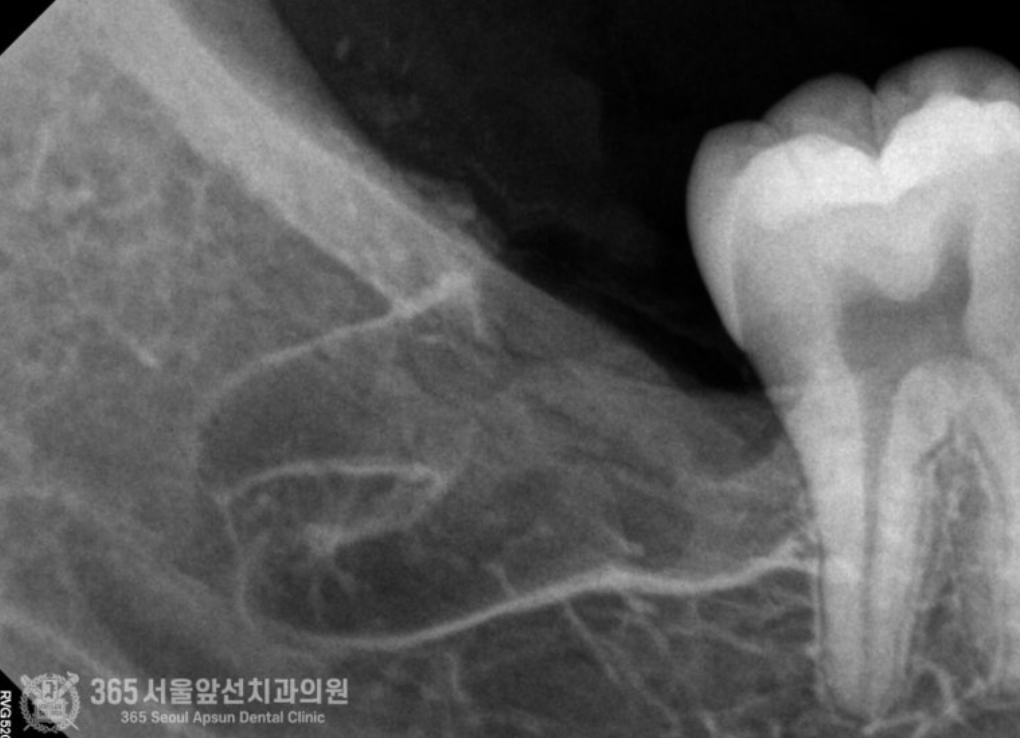

치아교정 전에 양쪽 매복사랑니 발치하고 싶어요. 안녕하세요. 간석동치과 365서울앞선치과의원입니다. 오늘 소개해드릴 치료 증례는 아래턱 수평 매복 사랑니 발치 증례입니다. 상기 환자분께서도 그러한 이유에서 사랑니 발치를 원하셔서 진행하기로 했습니다 ㅎㅎ 촬영일시 : 2024.08.13. 처음 내원 당시 엑스레이 사진입니다. 입안에서 오른쪽 아래턱(사진상 왼쪽 아래 빨간원)에 수평으로 매복된 사랑니가 관찰됩니다. 촬영일시 : 2024.08.13. 정밀한 작은 엑스레이를 촬영했습니다. 사진 상에서 아래쪽에 신경관이 지나가는게 관찰됩니다. 주의해서 발치해야겠습니다. 촬영일시 : 2024.08.13. 발치를 시작한지 6분만에 발치를 완료했습니다. 빠르고 정확한 발치를 통해 환자분의 고통을 줄여드릴 수 있었습니다 ㅎㅎ 촬영일시 : 2024.08.13. 매복사랑니를 세 조각으로 잘라서 발치를 진행해드렸고, 깔끔하게 절단된 사랑니 조각들이 보입니다. 빠르고 정확한 발치에 환자분께서도 만족하셨습니다. 오늘은 6분만에 아래턱 매복 사랑니 발치를 완료한 치료 증례를 소개해드렸습니다. 앞으로도 더 좋은 치료 증례로 찾아뵙겠습니다. 간석동치과 365서울앞선치과의원이었습니다. 감사합니다! [ 치료기간: 2024년 8월13일 ] ※ 365서울앞선치과의원의 모든 포스팅은 각 진료과 의료진이 직접 작성합니다. 365서울앞선치과의원 블로그의 임상 케이스 게시물은 환자분께 의학적으로 정확하고 상세한 정보를 드리기 위해 각 진료과 의료진이 직접 작성하며, 모든 증례 사진은 본원 의료진이 직접 시술한 증례를 촬영한 것으로, 의료법 제23조, 제56조에 의거하며 환자분의 동의를 얻어 포스팅에 사용하였습니다. 또한 해당 케이스는 본 환자분의 치료 결과이며, 환자 상태에 따라 치료의 결과는 달라질 수 있습니다. |